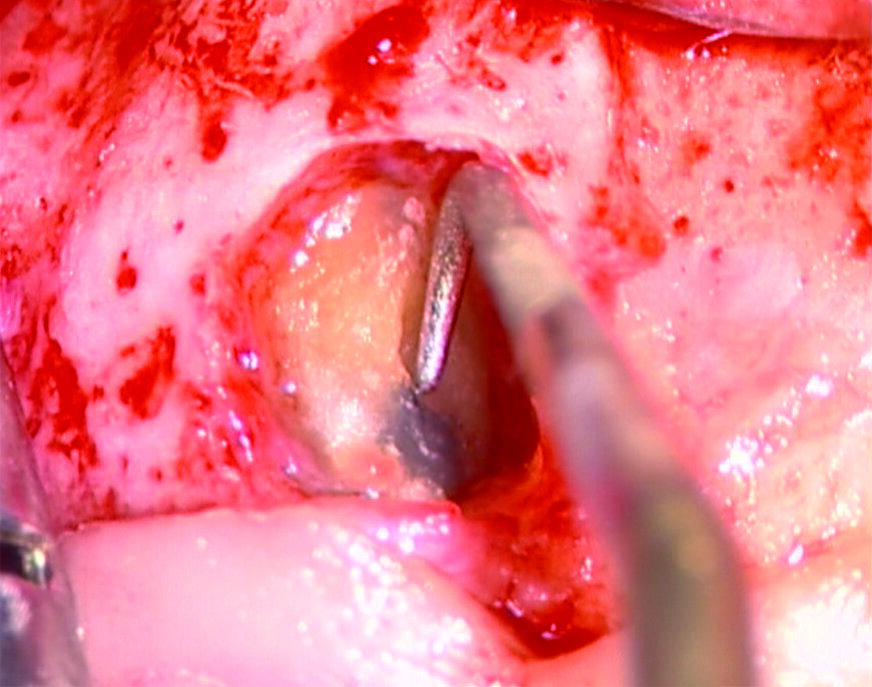

Tali perforazioni sono piuttosto frequenti a livello degli incisivi superiori, dove l’errore che più spesso viene commesso è rappresentato dall’utilizzo della fresa con eccessiva angolazione vestibolare. Perforazioni del terzo coronale possono anche accadere sul pavimento dei molari quando gli orifizi canalari vengono cercati in posti sbagliati. Tipiche sono le perforazioni nei molari superiori o inferiori, che avvengono per lo sfondamento del pavimento della camera pulpare (Figg. 3a-3i). Come conseguenza del trauma meccanico, si ha una rapida distruzione del legamento parodontale. L’osso alveolare immediatamente adiacente alla perforazione si riassorbe con conseguente perdita verticale di osso. Il processo infiammatorio quindi si estende coronalmente lungo le fibre del legamento parodontale, con distruzione del legamento, dell’osso alveolare e delle fibre gengivali sopracrestali. Come conseguenza di ciò, si ha la migrazione apicale dell’attacco epiteliale e le formazione di un grave difetto parodontale9.

Riparazione delle perforazioni mediante l’uso di MTA

La prognosi delle perforazioni è enormemente migliorata dopo l’introduzione dell’utilizzo del microscopio operatorio14 e del materiale biocompatibile MTA15, messo a punto da Torabinejad e coll.16 circa a metà degli anni ’90. Si tratta di un cemento endodontico estremamente biocompatibile, idrofilo e capace di stimolare processi di guarigione e osteogenesi17, 18. È una polvere di fini triossidi e altre particelle idrofile che induriscono in presenza di umidità. L’idratazione della polvere, infatti, dà luogo ad un gel colloidale che solidifica in una struttura dura in circa 3/4 ore. Tale cemento è diverso da tutti gli altri materiali usati per la sua biocompatibilità, per la sua attività antibatterica, per il suo adattamento marginale, per le sue capacità sigillanti ma soprattutto perché è idrofilo e quindi è resistente all’umidità.

- Applicare 2-3 mm di spessore di MTA;

- Controllare radiograficamente il corretto posizionamento del materiale;